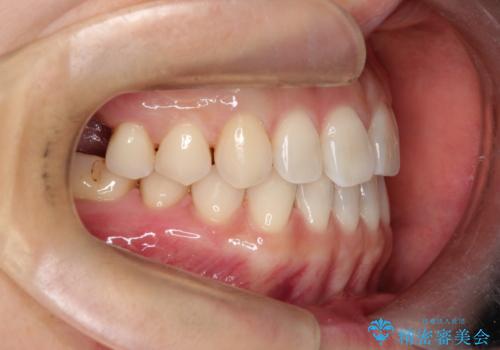

【インビザラインで再矯正】マウスピース矯正で隙間を閉じたい

- 過去に矯正を行ったあと、前歯の後戻りを主訴に来院されました。

マウスピース矯正にて隙間を閉じる計画をたて、治療を行いました。